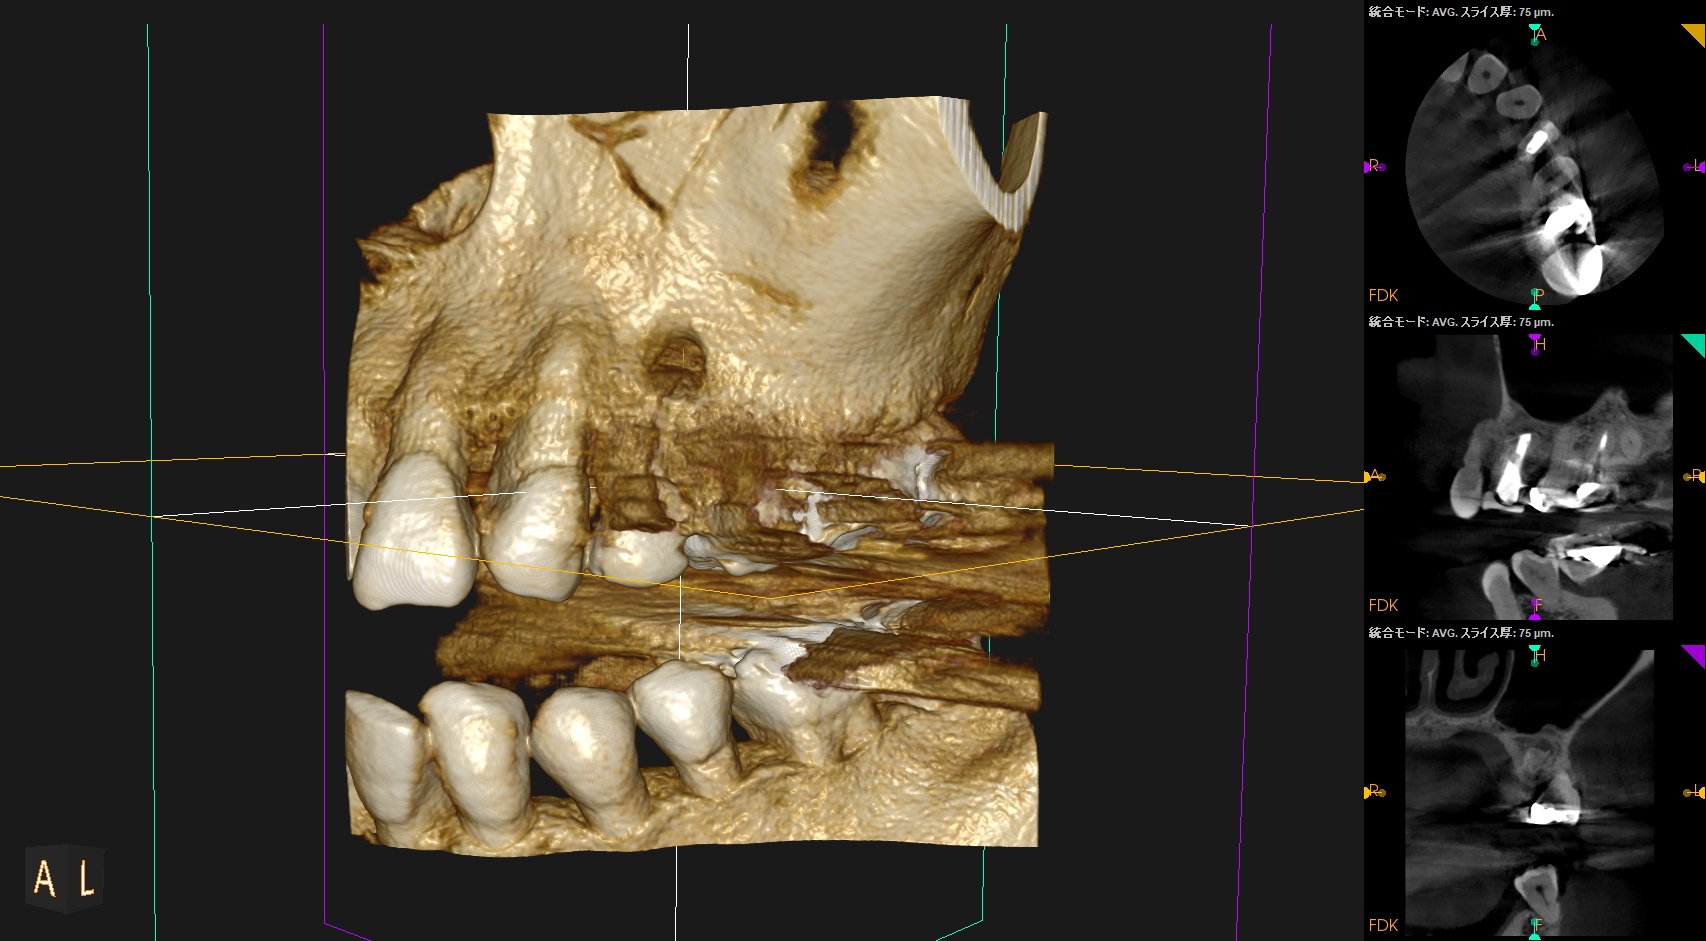

#12 Apicoectomy 6M recall(2026.2.18)

初診時と比較した。

問題は大きく解決している。

最終補綴も問題がないだろう。

次回はさらに半年後の1yr recallである。